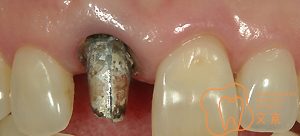

■歯の基礎となるコア 接着性能を向上させたファイバーコア

■根管治療は歯の寿命を左右する

■前歯が折れてしまった、、、